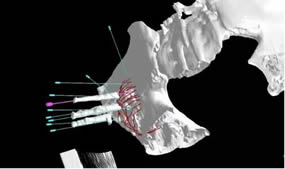

6月24日,我院介入科林征宇主任、陈锦主治医师及其团队成功开展福建省首例3D打印导向模板引导下的放射性粒子植入手术。此患者为男性,40岁,肝癌术后1年余,发现左髂骨转癌半年,行外放疗+索拉非尼靶向治疗后肿瘤残留,症状表现为左髋部疼痛,站立及行走时明显,影响日常生活及睡眠。根据患者术前的CT图像,医疗团队在PROWESS TPS软件中确定肿瘤的大小、位置及与危及器官的毗邻关系,利用计算机模拟设计一个与体表完全吻合的模板,并在模板上设计出植入粒子的“针道”,按照瘤体照射剂量的TPS计划设计每个“针道”的深度、角度及植入粒子的数目,精心的术前准备使得术后结果与术前计划高度吻合,做到了更加便捷、精准、微创,使瘤体局部放射学剂量最优化。

3D打印模板引导下精准施术

术前设计进针路线和粒子规划